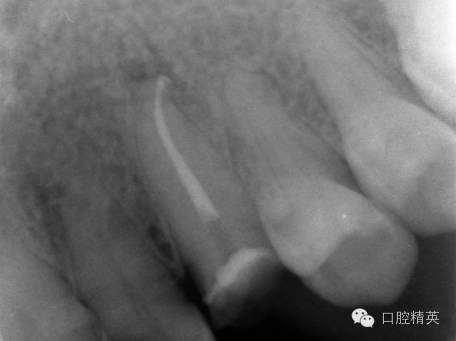

圖3 根管治療后X片